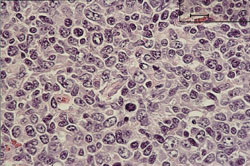

Den histopatologiske klassifisering ble utført ved Laboratorium for patologi, Vest-Agder sykehus, og malignitetsgradering ble bestemt på grunnlag av morfologi og immunhistokjemiske funn. Alle tilfeller ble klassifisert i henhold til både Kiel-klassifikasjonen og den europeisk-amerikanske lymfomklassifikasjonen Revised European American Lymphoma Classification (REAL) (7 – 9). Sammen med betegnelsene lavgradig (fig 1) og høygradig (fig 2) malignt lymfom var dette klassifisering som ble brukt i perioden for innsamlingen av vårt materiale.